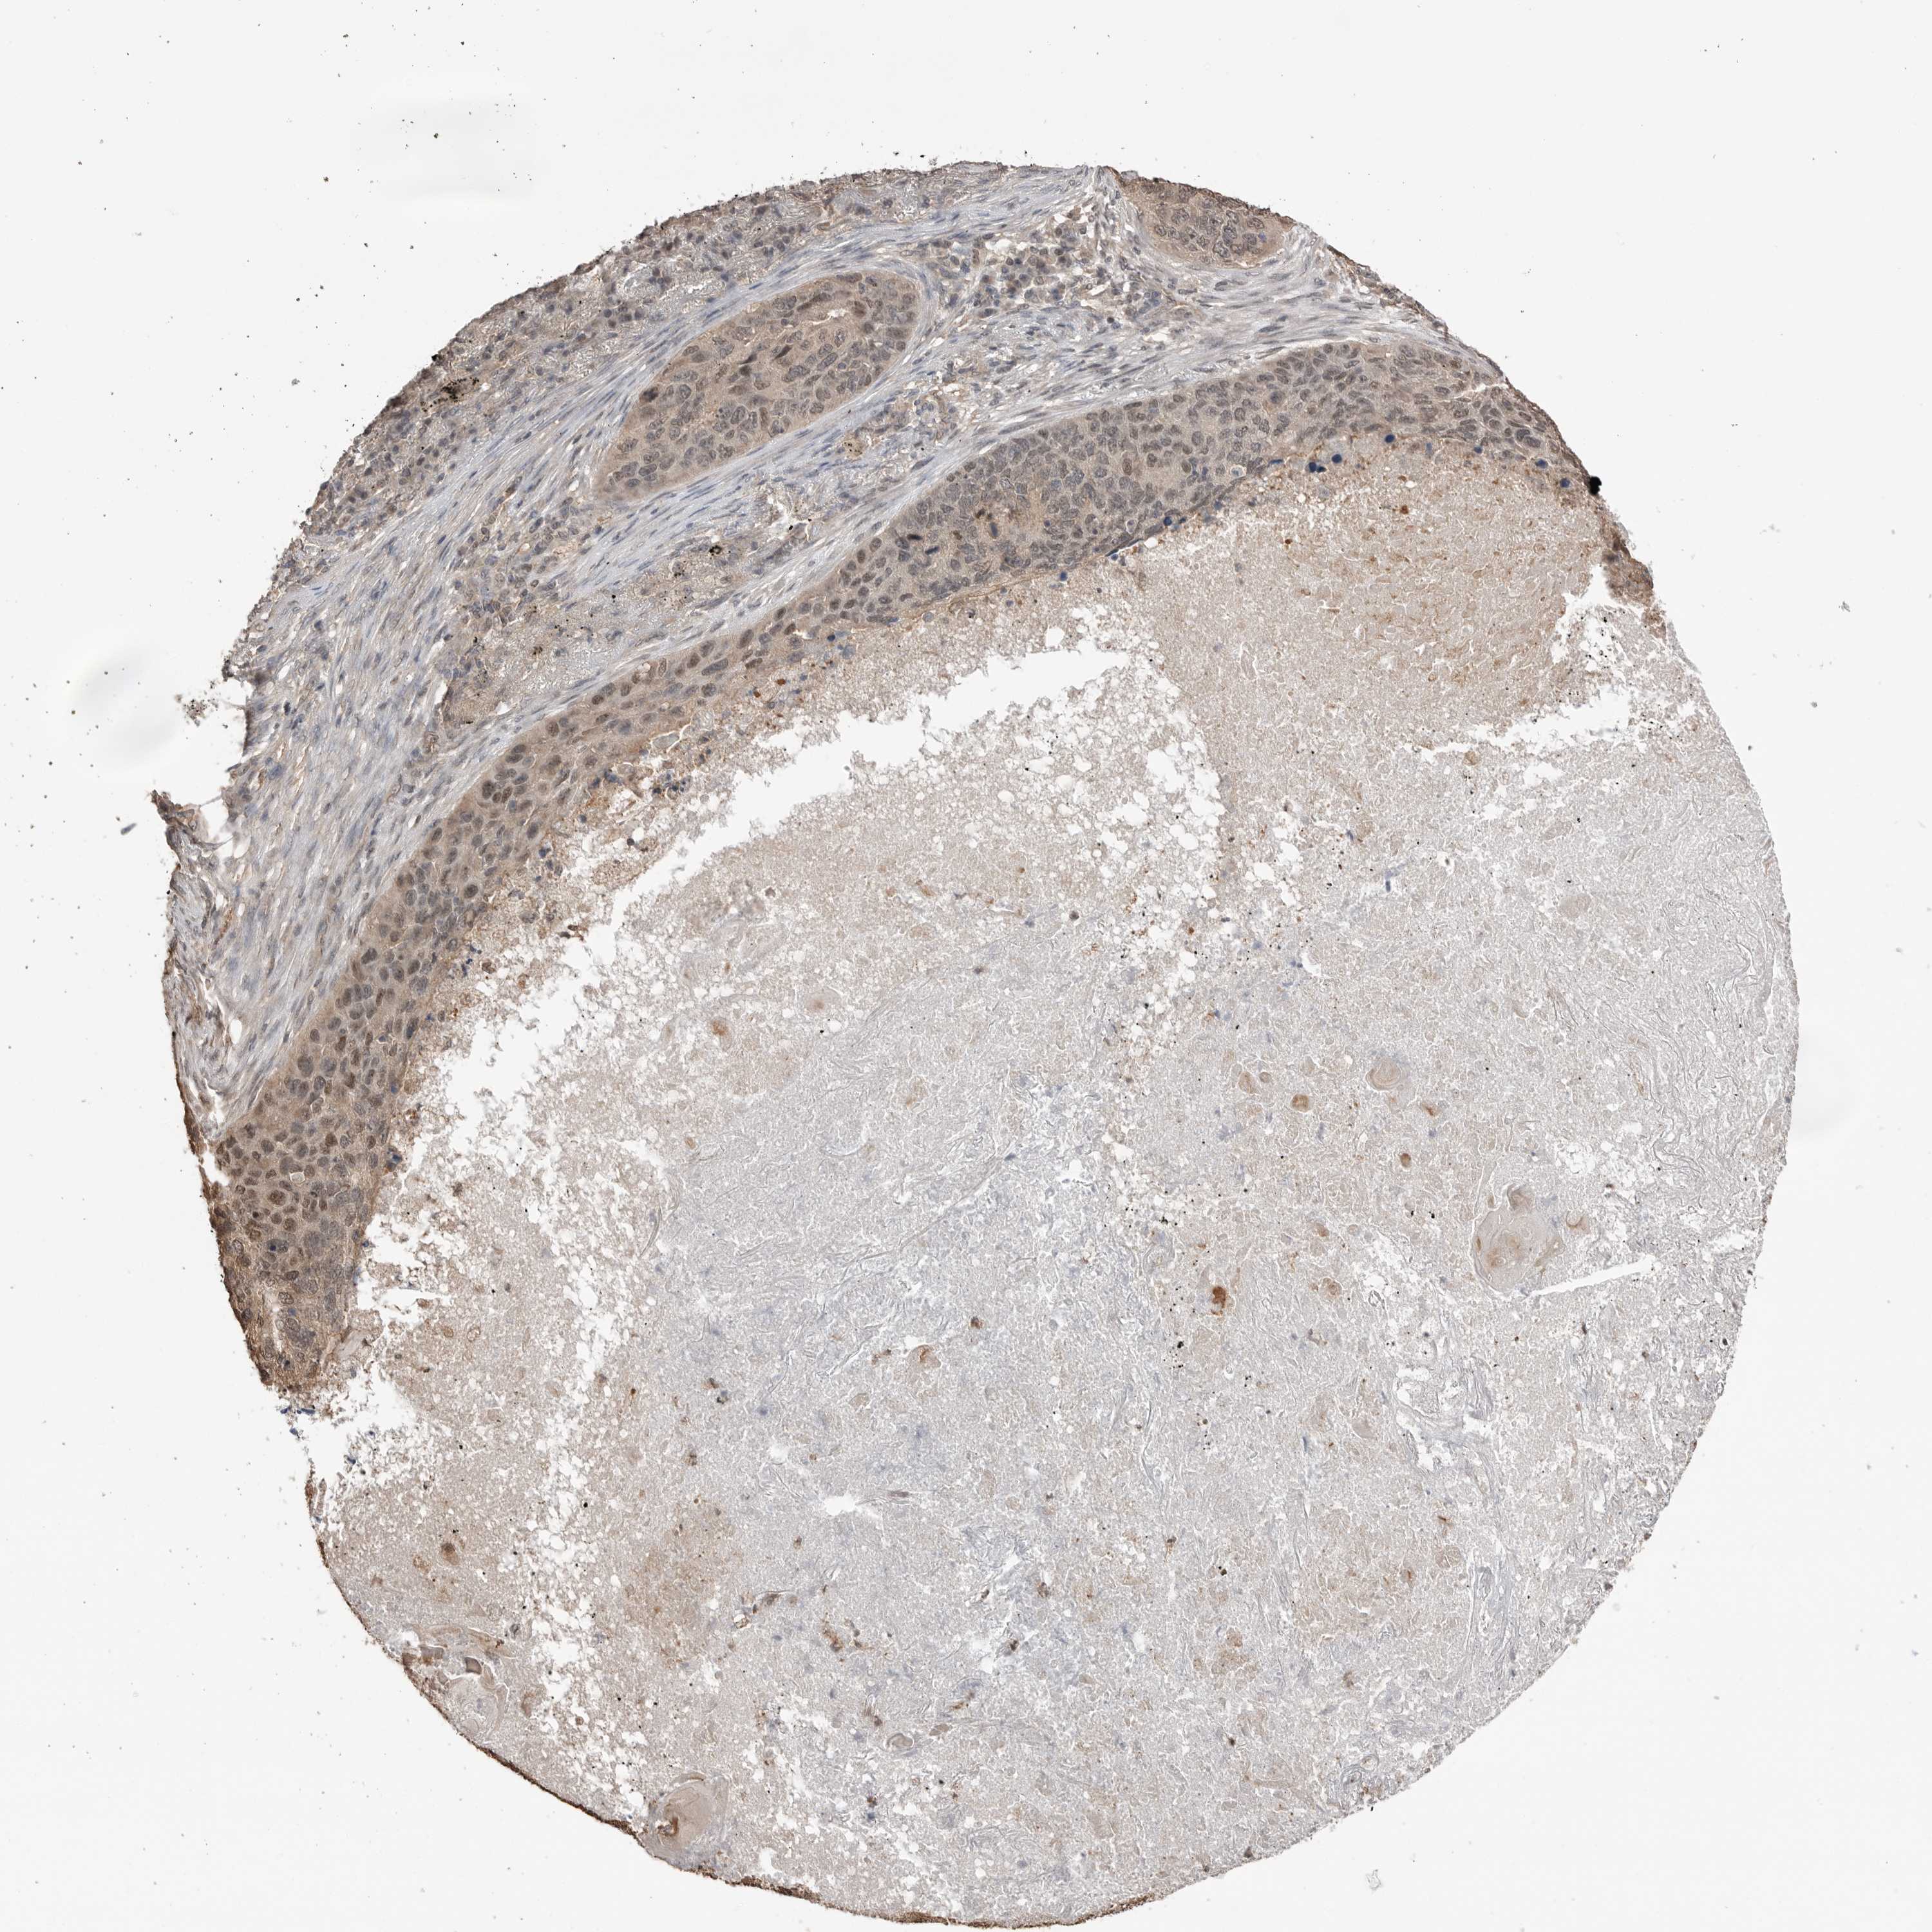

LUNG ADENOCARCINOMA (TCGA) - Interactive survival scatter ploti

The Survival Scatter plot shows the clinical status (i.e. dead or alive) for all individuals in the patient cohort, based on the same data that underlies the corresponding Kaplan-Meier plots. Patients that are alive at last time for follow-up are shown in blue and patients who have died during the study are shown in red.

The x-axis shows the expression levels (FPKM) of the investigated gene in the tumor tissue at the time of diagnosis. The y-axis shows the follow-up time after diagnosis (years). Both axes are complimented with kernel density curves demonstrating the data density over the axes. The top density plot shows the expression levels (FPKM) distribution among dead (red) and alive patients (blue). The right density plot shows the data density of the survived years of dead patients with high and low expression levels respectively, stratified using the cutoff indicated by the vertical dashed line through the Survival Scatter plot. This cutoff is automatically defined based on the FPKM cutoff that minimizes the p-score. The cutoff can be changed by dragging the vertical line or by entering a cutoff value in the square labeled "Current cut-off".

Under the Survival Scatter plot the p-score landscape (black curve; left axis) is shown together with dead median separation (red curve; right axis). Dead median separation is the difference in median mRNA expression between patients who have died with high and low expression, respectively. It is calculated as follows: median FPKM expression of dead patients with high expression - median FPKM expression of dead patients with low expression. This is intended to aid the user in visually exploring custom cutoffs and the associated p-scores and dead median separation.

Individual patient data is displayed and can be filtered by clicking on one or more of the category buttons on the top of the page. Categories describing expression level and patient information include: high, low, alive, dead, female, male and tumor stages. The scale of the x-axis can be toggled between linear and log-scale by clicking on the "x log" button. Mouse-over function shows TCGA ID, patient information and mRNA expression (FPKM) for each patient.

& Survival analysisi

Kaplan-Meier plots summarize results from analysis of correlation between mRNA expression level and patient survival. Patients were divided based on level of expression into one of the two groups "low" (under cut off) or "high" (over cut off). X-axis shows time for survival (years) and y-axis shows the probability of survival, where 1.0 corresponds to 100 percent.

PEAK1 is not prognostic in Lung Adenocarcinoma (TCGA)

Best expression cut offi

Based on the FPKM value of each gene, patients were classified into two groups and association between prognosis (survival) and gene expression (FPKM) was examined. The best expression cut-off refers the FPKM value that yields maximal difference with regard to survival between the two groups at the lowest log-rank P-value. Best expression cut-off was selected based on survival analysis .

When clicking on this number, the vertical dashed line indicating cut-off, the interactive survival plot, and the Kaplan-Meier curve will be adjusted to show results based on the best expression cut-off.

: 4.68

P scorei

Log-rank P value for Kaplan-Meier plot showing results from analysis of correlation between mRNA expression level and patient survival.

N/A

TCGA RNA samplesi

RNA-seq data is reported as average FPKM (number Fragments Per Kilobase of exon per Million reads), generated by the The Cancer Genome Atlas (TCGA) .

Normal distribution across the dataset is visualized with box plots, shown as median and 25th and 75th percentiles. Points are displayed as outliers if they are above or below 1.5 times the interquartile range. FPKM values of the individual samples are presented next to the box plot.

Average pTPM 5.3

Number of samples 497